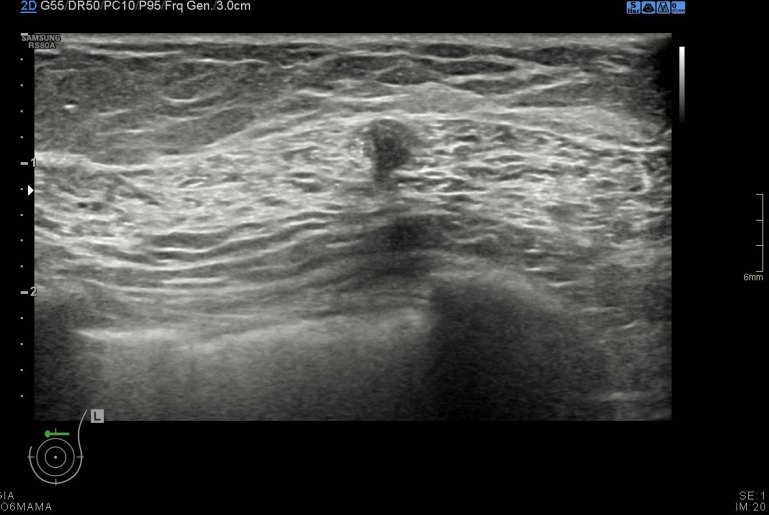

Durante la exploración se observan cambios secundarios a mastectomía bilateral, pero en línea intercuadrántica superior de mama izquierda, en el espesor del musculatura pectoral vi un nódulo hipoecogénico de 6 mm de bordes irregulares (imágenes 2 a 5) que me pareció muy feo, me asusté y aunque no era palpable inmediatamente se lo comenté a la doctora encargada de la exploración, lo calificó de Birads 4C y le pidió resonancia magnética.

Lo primero de todo la anatomía de la ecoestructura, es vital para comprender lo que se ve. Además ligada con la semiología, puedes ver como la grasa de la reconstrucción con colgajo abdominal es muy parecida a la grasa normal que puedes encontrar en la mama que no ha sido intervenida. Siempre tener una visión global de la ecoarquitectura, conocimiento de la normalidad de todos los tejidos englobados en la ecografía y eventual mamografía de la mama para poder localizar cambios anómalos.

Tras los estudios posteriores realizados como ampliación de estudio, arrojaron cambios postquirúrgicos en el pectoral que explicaban la imagen descrita anteriormente y que puedes ver en la imágenes que te he puesto.

Afortunadamente fueron buenas noticias, el resultado fue benigno a pesar de la alta sospecha, a consecuencia de los cambios posquirúrgicos que afectaban a la porción muscular de la exploración ecográfica. Siempre en mamas operadas los cambios postquirúrgicos pueden ofrecer zona llamativas, nosotros siempre atentos y ante cualquier duda lo dejamos reflejado en el pre-informe o se lo contamos directamente a la radióloga responsable, nunca nos quedamos con dudas, siempre documentar los hallazgos correctamente con máxima calidad de imagen, siempre es nuestra carta de presentación.